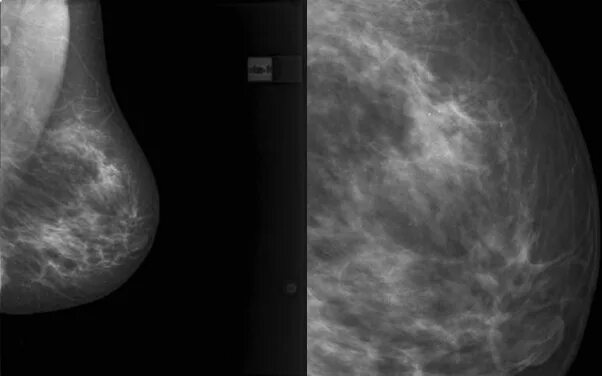

Отечная форма рака молочной